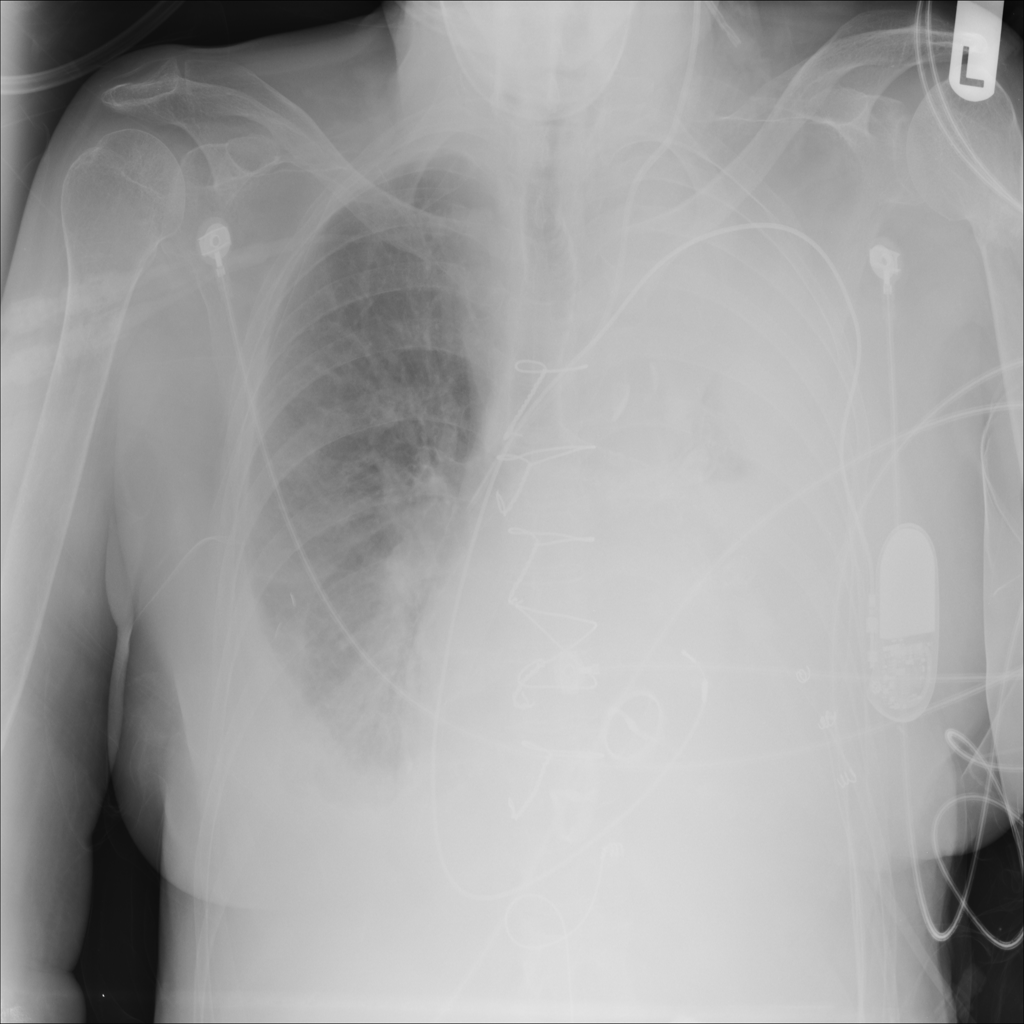

Pleural Effusion

Pleural effusion means extra fluid has collected around the lung in the pleural space. It can happen with heart problems, infection, inflammation, or other underlying conditions.

Showing up to 90 reference images for Effusion.

PAT-4639 · IMG-021Effusion

PAT-4639 · IMG-021

PA